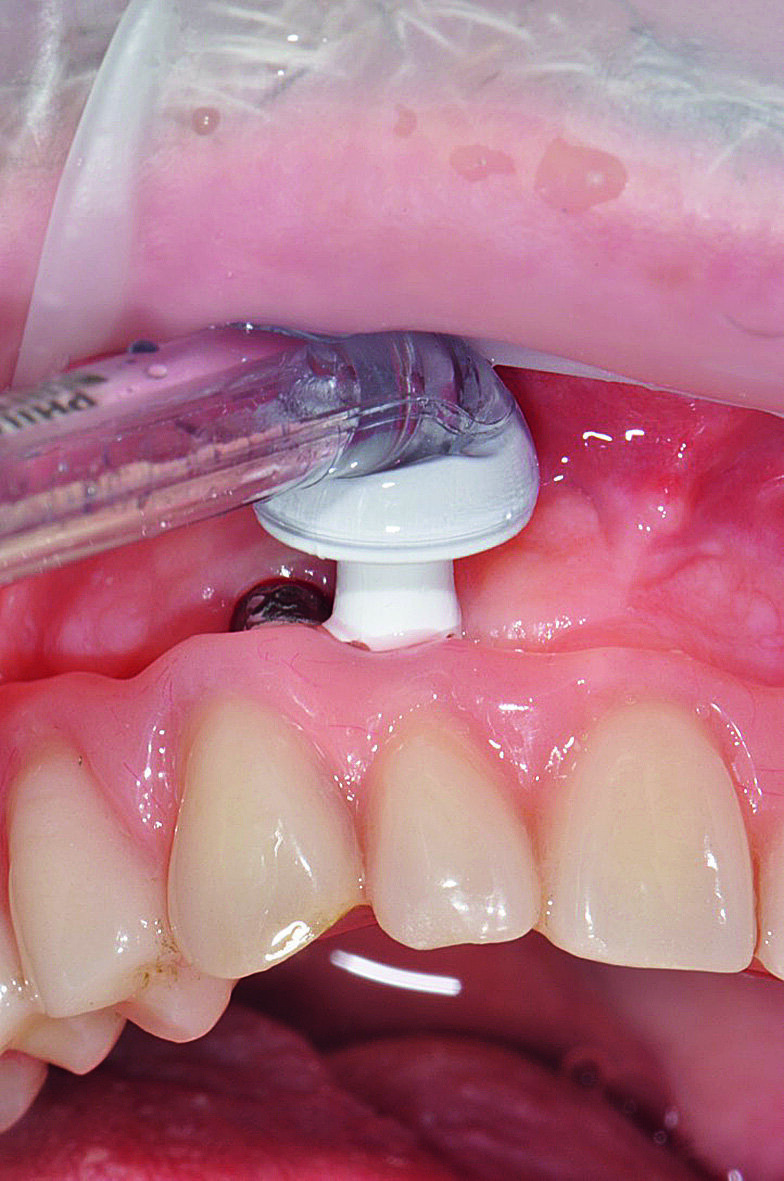

Figs. 1a : Implant en position 14 affecté par une péri-implantite : sondage péri-implantaire avec la couronne prothétique in situ

Fig b : Implant en position 14 affecté par une péri-implantite : sondage péri-implantaire après retrait de la couronne prothétique.

| Figs. 4a : Soins péri-implantaires à domicile avec AirFloss (Philips),